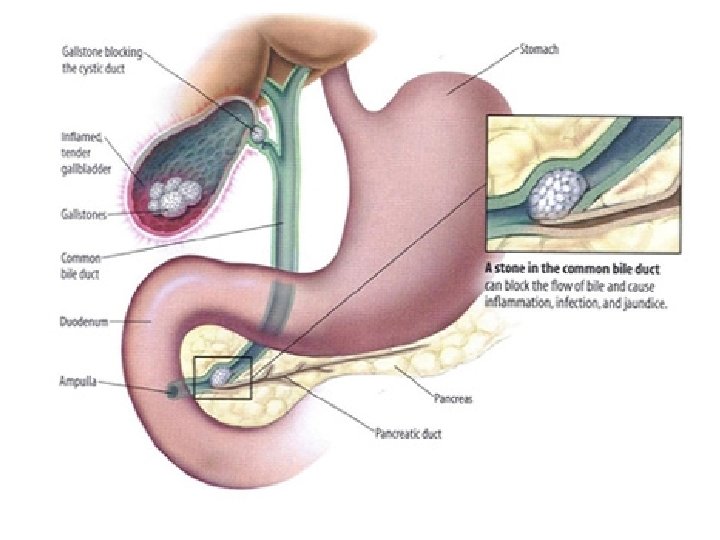

• ETIOLOGJIA: Mendohet se 90% e rasteve te kolecistitit vijne nga kalkuloza biliare. Te tjera: - bllokim i rrugeve biliare nga aderanca me organet fqinje, - periduodeniti, - ulcera peptike, - infiltrimi neoplazik. 10% jane nga shkaqe akalkuloze: brucelloza, ethja tifoide, mononukleoza infektive, salmonellozat etj.

• KLINIKA: - Shenja kryesore eshte dhimbja abdominale e forte qe lokalizohet me veshtiresi nga i semuri. - Dhimbja: fillon ne regionin epigastrik, mund te perhapet edhe ne shpine ose ne shpatullen e djathte, por kryesisht perqendrohet ne kuadrantin superior dexter. - Eshte nje dhimbje me intensitet ne rritje. - Kjo dhimbje pasqyron tensionin dhe inflamacionin e mureve te kolecistes, si pasoje e obstruksionit kalkuloz te duktusit cistik.